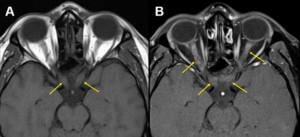

A 30-year-old Hispanic male presented with sudden, painful vision loss over 3 days in both eyes. He reported mild photophobia, pain on eye movement, and that vision in his right eye was worse than in his left eye. The patient reported he had presented to a local emergency department 2 days prior where computed tomography of his brain was found to be normal. However, he sought a second opinion at our clinic because his vision continued to decline. His ocular and medical history were unremarkable. Medications included acetaminophen 500 mg as needed. He had no known allergies to medications and his social history was unremarkable. Entering visual acuity was 20/800 in the right eye and 20/125 in the left eye, with no improvement with pinhole testing. Pupils were equal in size, round and responsive to light. Swinging flashlight test revealed a right relative afferent pupillary defect (RAPD). Extraocular muscle motility was full in both eyes, but the patient reported pain with eye movement in all gazes. Slit lamp examination was unremarkable, and intraocular pressure (IOP) measured 12 mmHg in each eye with Goldmann applanation tonometry. Dilated fundus exam revealed bilateral ON edema (Figure 1). The macula and peripheral retina were unremarkable in both eyes. Threshold 30-2 visual field testing was performed and showed overall depression in both eyes (Figure 2). Baseline spectral-domain optical coherence tomography (OCT) of the optic nerves was obtained. A large amount of retinal nerve fiber layer (RNFL) thickening was noted in the right eye, more so along the superior and inferior portions of the optic nerve head. Thickening was also noted inferiorly in the left eye. Unfortunately, the data for the superior portion of the left optic nerve was not reliable due to scanning artifact (Figure 3). Emergency magnetic resonance imaging (MRI) revealed bilateral optic nerve enhancement consistent with bilateral ON (Figure 4). Given the bilateral ON findings and entering visual acuities, NMOSD was suspected and confirmed with positive aquaporin-4 immunoglobulin G (AQP4-IgG) titers.

![]() Figure 4. A: Orbital axial magnetic resonance imaging (MRI) without contrast showing posterior optic nerve hyperintensities (yellow arrows) suggestive of bilateral optic neuritis. B: Orbital axial MRI with contrast and fat suppression showing extensive bilateral enhancement of the optic nerves (yellow arrows) confirming the diagnosis of bilateral optic neuritis. Click to enlarge |